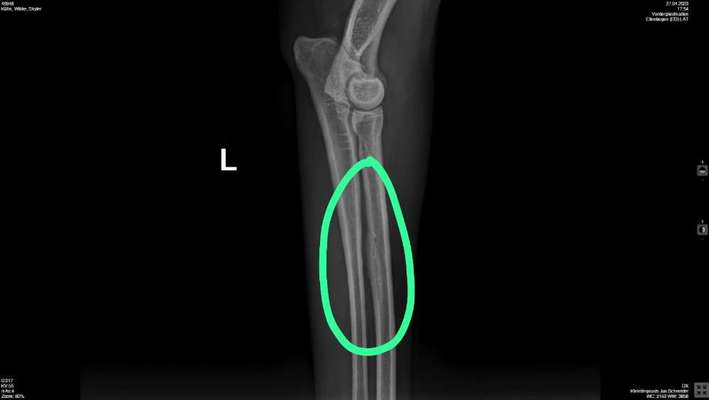

Seit Samstag humpelt Skyler immer mal wieder. Am Montag waren wir beim Tierarzt. Es wurde erstmal nichts gravierendes festgestellt. Sie bekam dann erstmal ein Schmerzmittel und wir sollen weiter beobachten. Leider trat bisher keine Besserung ein. Vor allem nach längerem Liegen wird es eher schlimmer. Gestern sind wir dann nochmal zum Tierarzt. Dort wurden die Vorderbeine geröntgt. Sie hat an beiden Vorderbeinen Veränderungen am Knochen. Was genau das nun ist wissen wir bisher nicht. Müssen jetzt noch zu einem Spezialisten. Leider haben wir erst am 9.5. einen Termin bekommen. Ich bin im Moment ziemlich traurig. Die Maus ist noch nicht mal drei Jahre alt und dann schon sowas. Habt ihr noch Ideen wie ich der Maus bis dahin das Leben erleichtern kann?

Heute waren wir bei einem Orthopäden/Chirurg für Hunde. Erstmal ist im Moment in nicht deutlich feststellbar ob Skyler noch Schmerzen hätten da sie ja unter Schmerzmitteln steht. Das Röntgenbild ist wohl nicht schlimm. Das was so aufgeschwemmt aussiehst ist die Stelle, wo die Sehne mit dem Knochen verbunden ist. Es ist bei Skyler deutlich ausgeprägter als normal. Nur bei der Untersuchung war die linke Schulter etwas in der Bewegung eingeschränkt. Wir setzen jetzt erstmal die Schmerzmittel ab, um rauszufinden, ob die Schmerzen tatsächlich weg sind oder ob sie nur "unterdrückt" sind. Wenn kein humpeln mehr kommt, alles gut, wenn das humpeln wieder los geht, haben wir nächsten Dienstag einen Termin, an dem dann in Sedierung die Schulter genauer betrachtet wird. Also weiter Daumen drücken.